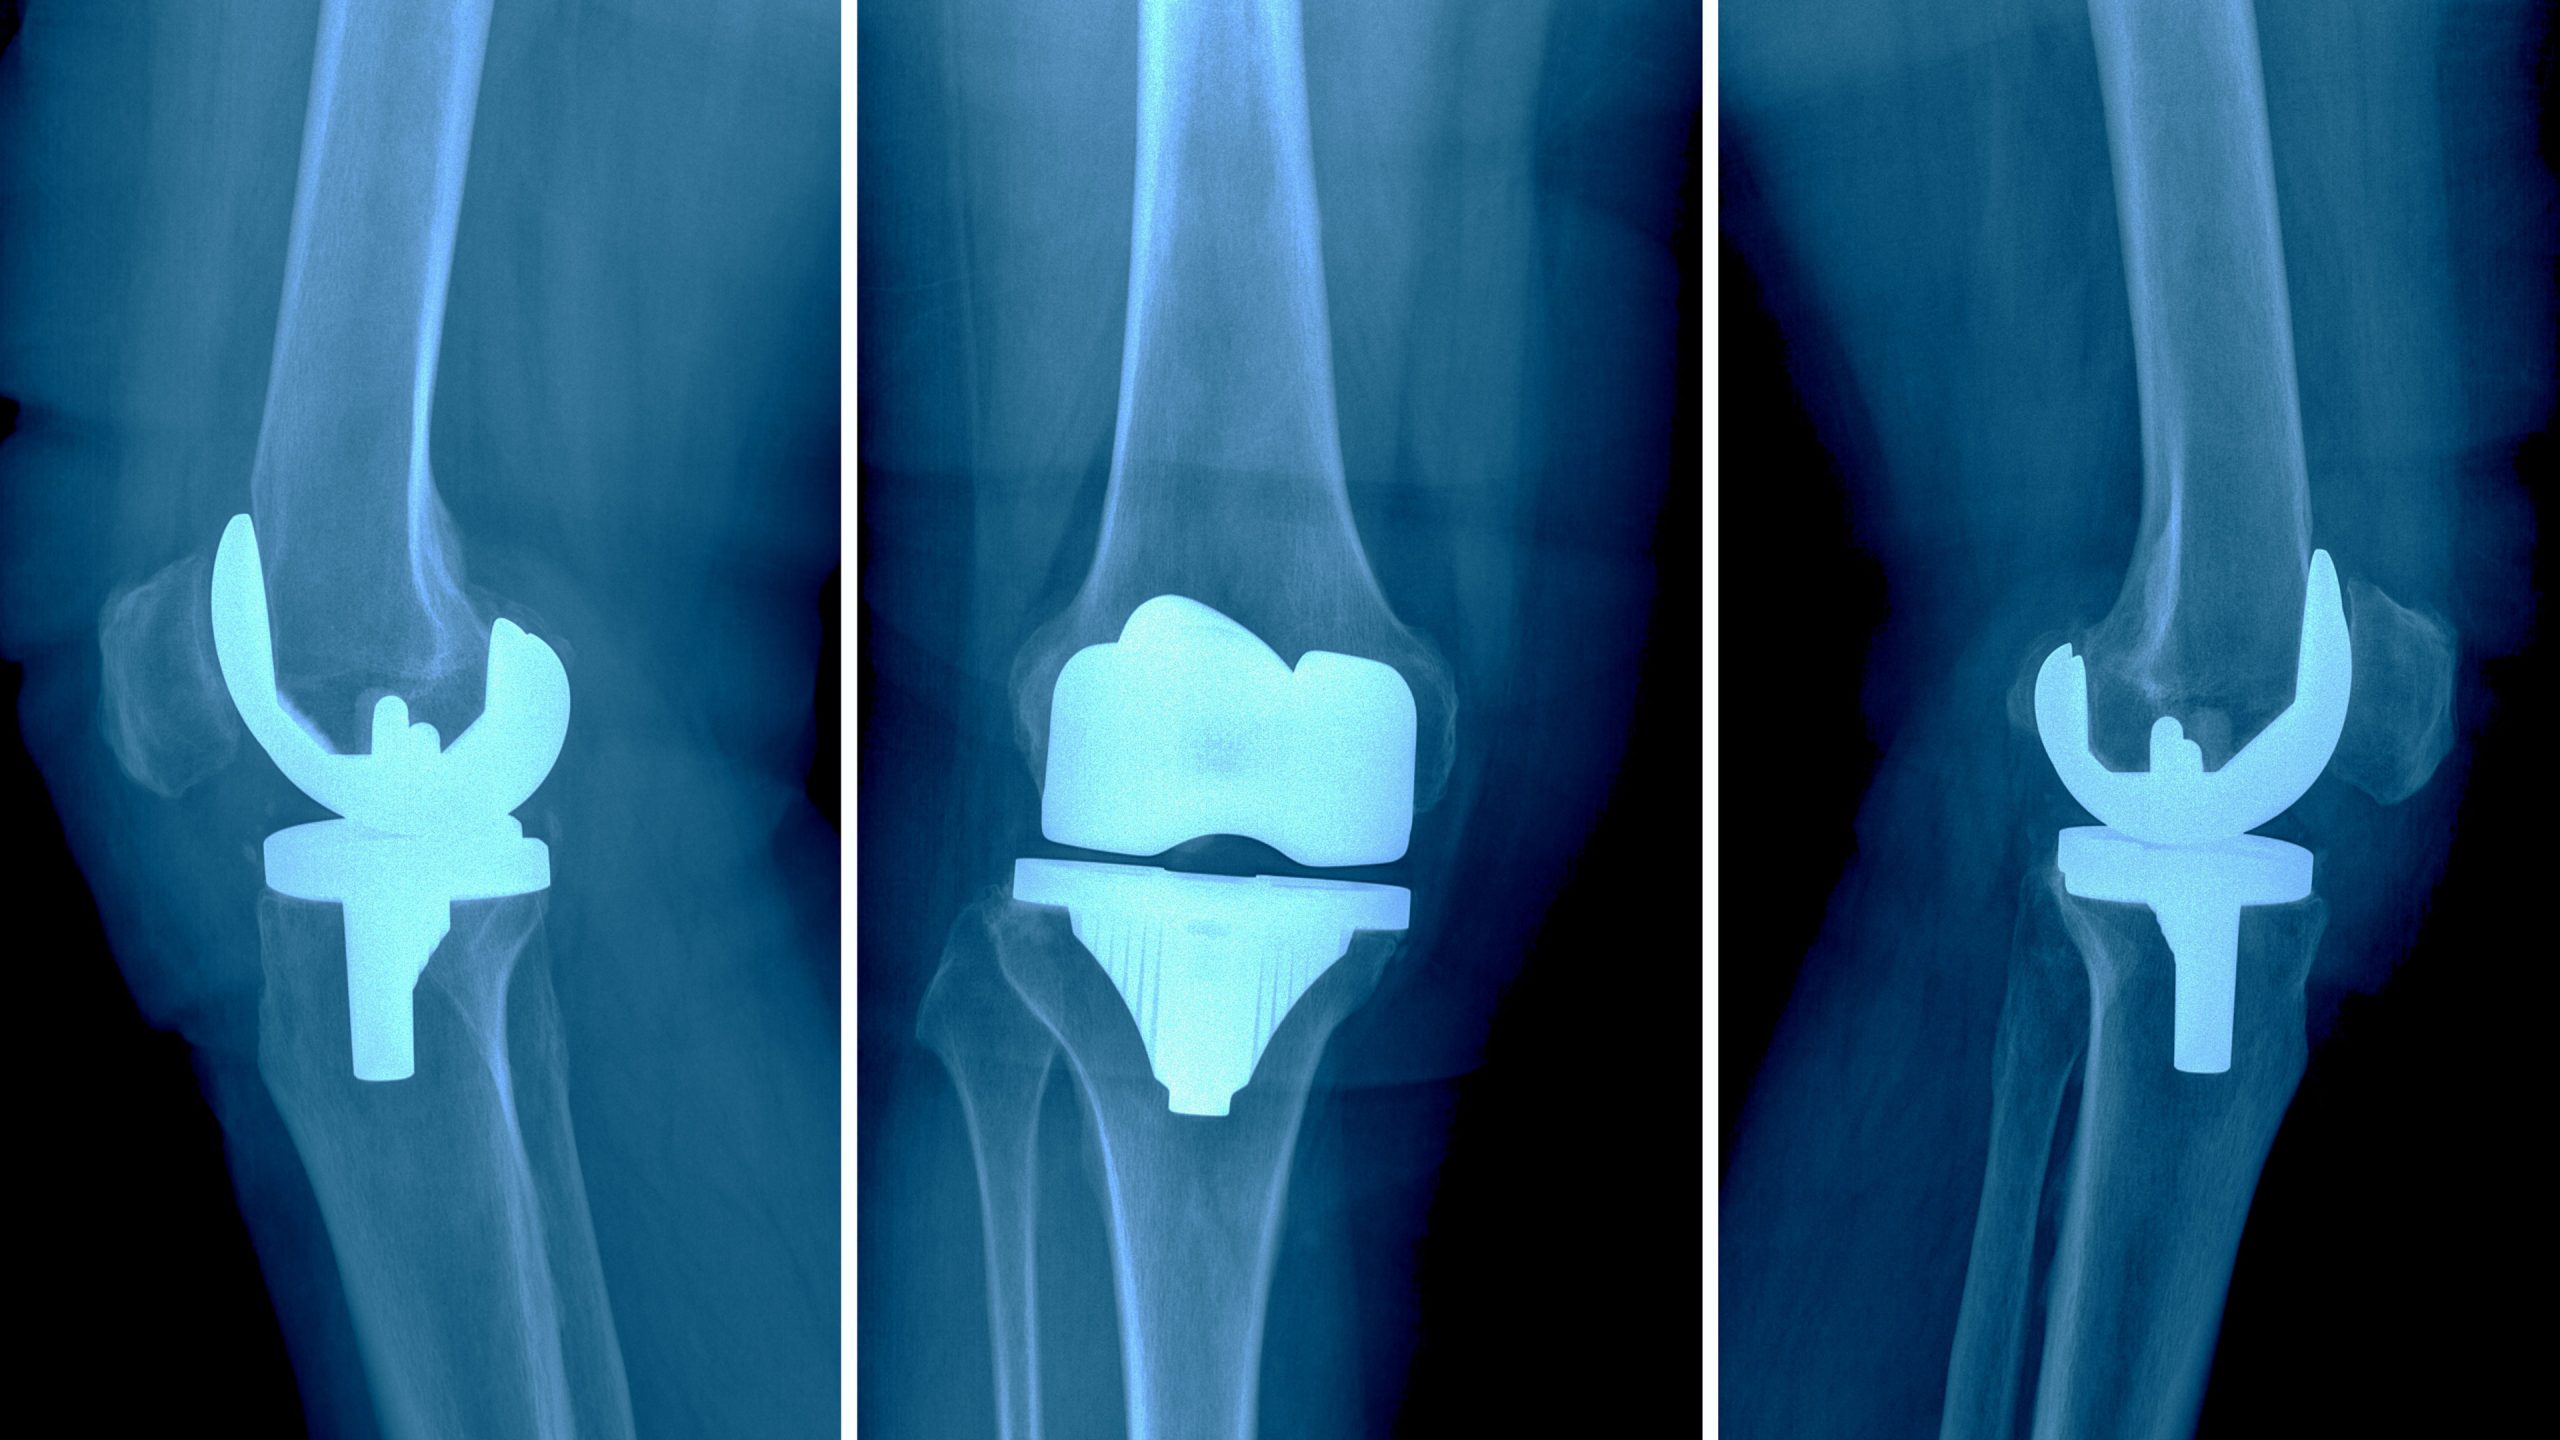

There are two main types of knee replacement procedures: total knee replacement (TKR) and partial knee replacement (PKR). In a TKR, the entire knee joint is replaced, including the surfaces of the femur, tibia, and patella. In contrast, a PKR involves replacing only the damaged portion of the knee, preserving as much of the healthy bone and tissue as possible. The choice of procedure depends on the extent of the damage and the patient’s overall condition.

Modern knee replacement surgery often utilizes minimally invasive techniques and advanced prosthetic materials. Surgeons may use robotic-assisted technology for precise alignment of the artificial components, leading to improved outcomes and longevity of the implants. The materials used in the prosthetics, typically metal alloys and high-grade plastics, are designed to mimic the natural movement and durability of the knee joint.